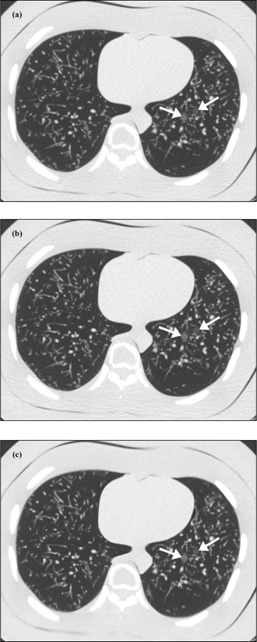

When comparing the mean reader ratings of nodule definition, the ratings for solid nodules were generally higher than for GGOs (for a given mAs and reconstruction technique). Furthermore, the mean reader ratings for the high attenuation GGOs were generally higher than for the low attenuation GGOs. With respect to nodule size, the ratings for nodules larger than 8 mm were generally the same or higher than those for nodules 8 mm or smaller. Across all eight GGOs and all 12 nodules, the mean reader ratings when using 20 effective mAs (60% dose reduction relative to the clinical protocol) and ASIR or MBIR were not observed to be significantly less than a mean rating of “3.” However, in general, the readers had higher mean rating of nodule definition for images reconstructed with MBIR than with ASIR. Figure 2 shows axial views of the phantom scanned at the aforementioned low‐dose protocols alongside the clinical protocol.

Figure 2.

CT images of the multipurpose chest phantom showing the 8 mm low‐attenuation (anterior) and high‐attenuation (posterior) simulated ground‐glass opacities (GGOs). These images were acquired using (a) a clinical lung cancer screening protocol (51 effective mAs) and reconstructed with filtered back‐projection (FBP), or (b) and (c) a reduced tube current protocol (20 effective mAs) and reconstructed with adaptive statistical iterative reconstruction (ASIR) or model‐based iterative reconstruction (MBIR), respectively.